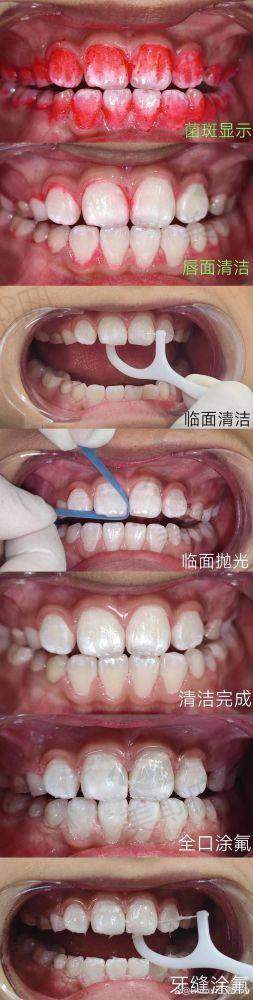

3. 注重儿童齿科的专科医院:一些牙科医院专门设立了儿童齿科科室,配备了专精的儿童牙科医生和适合儿童的诊疗设备。例如全好口腔,在儿童齿科方面有着丰富的经验,能够为儿童提供全口涂氟、树脂窝沟封闭、补牙、拔牙等服务,帮助儿童养成良好的口腔卫生习惯。

口腔儿童齿科价格表

全口涂氟 | 8元起 |

树脂窝沟封闭单颗 | 6元起 |

儿童玻璃补牙修补蛀牙 | 50元起 |

乳牙拔除 | 9.9元起 |